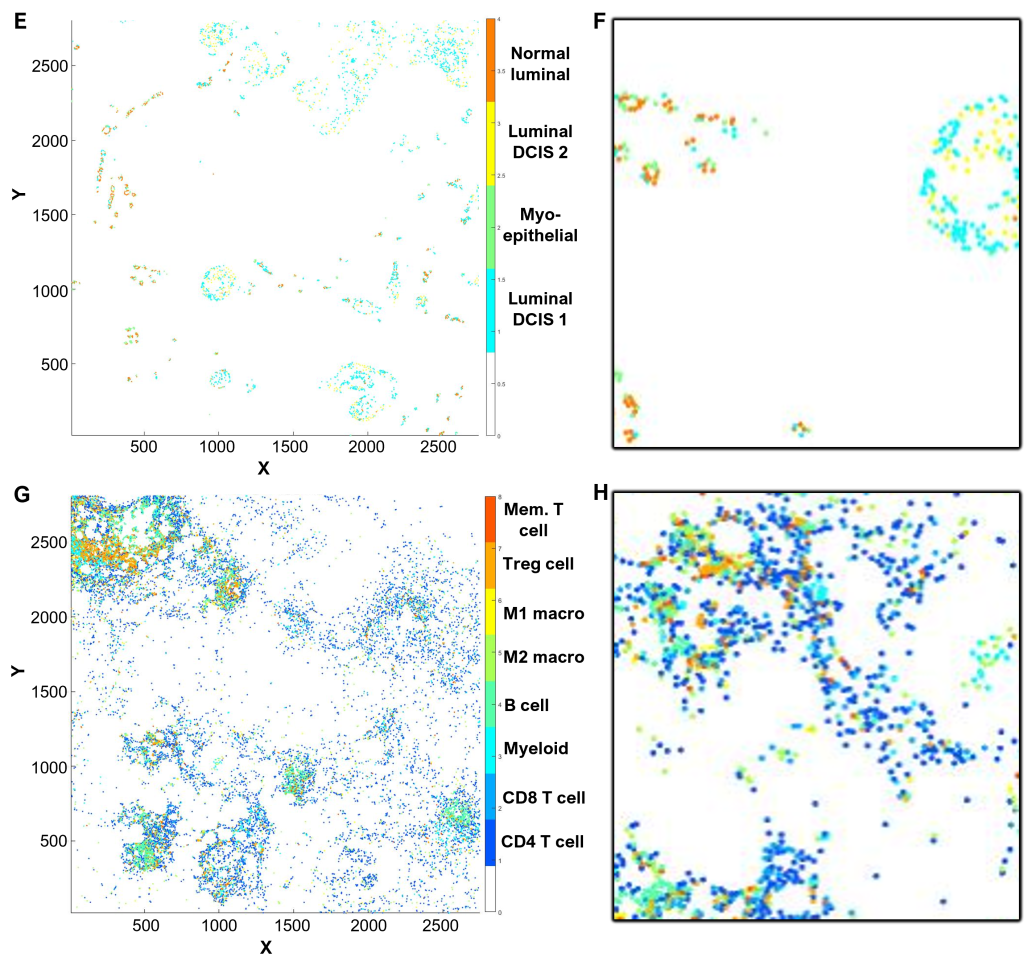

(I-J) Spatial profiling

Using CytoMAP software, cell phenotypes were further clustered according to xy coordinate location to define neighborhoods.

(I) DCIS in maroon (R7) is surrounded by immune cold micro-environment in blue (R1) separate form tertiary lymphoid structures in red (R6), orange (R5), and green (R3).

(J) Inset of (I), corresponding to the field of view in (B).